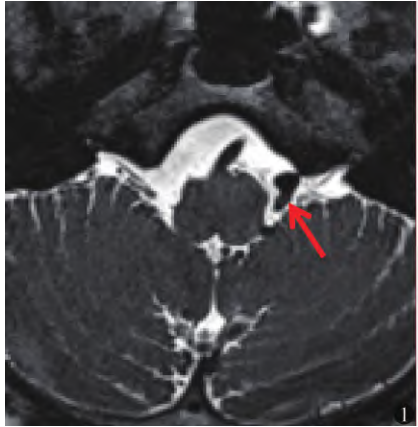

西安市臨潼67歲的朱女士,患舌咽神經(jīng)痛8年,左側(cè)咽喉部疼痛、并且向耳周?chē)派?,疼痛呈間歇刀割樣、針扎樣疼痛,吃飯、喝水像“吞刀片”樣痛苦,只能每次服用藥物后才能進(jìn)食,病因由于左側(cè)小腦后下動(dòng)脈壓迫舌咽神經(jīng)出腦干處導(dǎo)致,在西安交大一附院神經(jīng)外科顱神經(jīng)疾病專(zhuān)家組姜海濤教授為她進(jìn)行顯微血管減壓手術(shù),術(shù)后疼痛消失。 舌咽神經(jīng)痛都屬于顱神經(jīng)疾病,即神經(jīng)受到了位置異常的血管的壓迫,時(shí)間長(zhǎng)了,就會(huì)對(duì)神經(jīng)表面的髓鞘造成破壞,出現(xiàn)“神經(jīng)短路”的情況。血管壓迫舌咽神經(jīng)出現(xiàn)了“舌咽神經(jīng)痛”,表現(xiàn)為舌根、咽喉、扁桃體、耳道深部刀割樣疼痛,吞咽、吃飯、喝水會(huì)觸發(fā)疼痛;針對(duì)于原發(fā)性舌咽神經(jīng)痛患者,唯有解除病因,方能達(dá)到根治的目的,顯微血管減壓手術(shù)(MVD)是唯一的方法。 顯微血管減壓手術(shù)如何進(jìn)行? 針對(duì)顱神經(jīng)的磁共振成像,顯示有明顯血管壓迫神經(jīng)出入腦干段(root exit zone,REZ)的神經(jīng)根的情況的患者,適用顯微血管減壓術(shù)手術(shù)治療,術(shù)中在顯微鏡的輔助下顯微鏡下探查舌咽神經(jīng)、責(zé)任血管,精準(zhǔn)找到位置異常的血管和神經(jīng),將血管和神經(jīng)用Teflon神經(jīng)墊棉,將其隔離、減壓,解除二者壓迫,從而達(dá)到治愈的目的。 西安交大一附院神經(jīng)外科顱神經(jīng)疾病專(zhuān)家組,明確的術(shù)前診斷評(píng)估、術(shù)中精準(zhǔn)解除所有責(zé)任血管與神經(jīng)壓迫,保障了治愈率高,神經(jīng)損傷和并發(fā)癥低的優(yōu)點(diǎn)。

在過(guò)去的一年,2021年度顱底顱神經(jīng)疾病專(zhuān)家組門(mén)診量1732人,其中顱神經(jīng)疾病三叉神經(jīng)痛、面肌痙攣及舌咽神經(jīng)痛的患者門(mén)診量752人,進(jìn)行顯微血管減壓手術(shù)治療的患者211例,這兩百多位患者來(lái)自全國(guó)各地,最遠(yuǎn)的來(lái)自新疆,有青海、河北、河南、云南、山西、甘肅、重慶、四川,近到西安、渭南、咸陽(yáng)、榆林等周邊地區(qū),有病程長(zhǎng)達(dá)二十多年都在受病痛折磨的患者,也有病程只有幾個(gè)月的,他們?cè)谶M(jìn)行手術(shù)治療后重新恢復(fù)健康!據(jù)統(tǒng)計(jì),2021年顱底與顱神經(jīng)疾病專(zhuān)家組全年完成手術(shù)347例,其中顱腦腫瘤77例,涉及垂體瘤、腦膜瘤、膠質(zhì)瘤、顱咽管瘤、橋小腦角占位、四腦室占位、聽(tīng)神經(jīng)瘤等;以及211例顯微血管減壓手術(shù)面肌痙攣、三叉神經(jīng)痛、舌咽神經(jīng)痛,術(shù)后及長(zhǎng)期隨訪其治療效果滿意率98.83%。一、三叉神經(jīng)痛的顯微血管減壓手術(shù)治療2021年度三叉神經(jīng)痛患者手術(shù)治療98例,聽(tīng)神經(jīng)瘤、腦膜瘤、膽脂瘤等后顱窩腫瘤繼發(fā)三叉神經(jīng)痛7人,顯微血管減壓手術(shù)治療有效率98.8%,治愈率91.7%。“手術(shù)不是簡(jiǎn)單的重復(fù),精益求精做好每一臺(tái)。從傳統(tǒng)技術(shù)改進(jìn)、新技術(shù)立項(xiàng)到神經(jīng)外科相關(guān)神經(jīng)內(nèi)鏡、多模態(tài)三D融合等技術(shù)更新,在大量臨床實(shí)踐中逐漸形成了獨(dú)有的手術(shù)特色,形成顯微血管減壓手術(shù)規(guī)范化及管理流程,從術(shù)前的明確診斷、責(zé)任血管及神經(jīng)的確定、術(shù)中最佳的視野暴露、術(shù)中所有責(zé)任血管不能遺漏、充分減壓、術(shù)中避免機(jī)械及血運(yùn)損傷,每一步都要更加精準(zhǔn),盡量提高M(jìn)VD手術(shù)的有效率、降低并發(fā)癥發(fā)生率仍是未來(lái)中國(guó)功能神經(jīng)外科醫(yī)生的主要努力方向”專(zhuān)家組姜海濤教授介紹。病例一:原發(fā)性三叉神經(jīng)痛1、山西省臨汾市52歲的李先生,2年前左側(cè)面部出現(xiàn)間斷性電擊樣疼痛,每天多次發(fā)作。每次疼痛持續(xù)數(shù)分鐘,為了能夠緩解劇烈疼痛,在當(dāng)?shù)蒯t(yī)院確診后服用卡馬西平藥物控制,雖然吃藥后疼痛有緩解,但是出現(xiàn)瞌睡、臉腫等藥物副反應(yīng),影響到他的生活。2、榆林神木58歲的劉女士,5年前右側(cè)面部疼痛,疼痛發(fā)作時(shí)呈針扎樣,吃飯或面部吹風(fēng)時(shí)出現(xiàn)疼痛,口服卡馬西平后緩解,隨著時(shí)間的推移,藥物治療效果越來(lái)越差,反復(fù)疼痛折磨讓她整晚睡不著覺(jué)。李先生與劉女士是典型的原發(fā)性三叉神經(jīng)痛患者,李先生疼痛主要分布左側(cè)面部V2、V3區(qū)域,劉女士主要是左側(cè)面部V2分布區(qū)域自發(fā)性疼痛。術(shù)中,李先生的責(zé)任血管為左側(cè)小腦上動(dòng)脈及巖靜脈,壓迫三叉神經(jīng)腦池段,劉女士責(zé)任血管為右側(cè)小腦上動(dòng)脈壓迫三叉神經(jīng)腦池段。術(shù)中用神經(jīng)墊棉將責(zé)任血管與三叉神經(jīng)隔離減壓后,病因解除,疼痛癥狀消失。李先生與劉女士術(shù)前與術(shù)后對(duì)比(視頻),視頻已征求患者同意發(fā)布病例二、腫瘤占位繼發(fā)三叉神經(jīng)痛32歲張先生,右側(cè)面部疼痛2年,右側(cè)顴部疼痛,頭顱DWI顯示橋小腦角區(qū)、橋前池及鞍上池異常,考慮表皮樣囊腫,入院評(píng)估,確診為膽脂瘤繼發(fā)三叉神經(jīng)痛。幕下開(kāi)顱右側(cè)橋小腦角腫瘤切除手術(shù),顯微鏡下探查右側(cè)橋小腦角區(qū),可見(jiàn)白色珍珠樣光澤腫物,沿神經(jīng)血管間隙生長(zhǎng),術(shù)中分塊清除腫瘤組織,同時(shí)解除三叉神經(jīng)受壓,術(shù)后疼痛癥狀消失。術(shù)前與術(shù)后癥狀對(duì)比(視頻),視頻已征求患者同意發(fā)布術(shù)前確立診斷及仔細(xì)甄別腦神經(jīng)疾患的原發(fā)特性至關(guān)重要,是MVD手術(shù)成功的第一步。臨床實(shí)踐中因診斷錯(cuò)誤而致MVD失敗的例子屢見(jiàn)不鮮。三叉神經(jīng)痛(TN)的多病因性導(dǎo)致了其診斷及鑒別診斷的困難性,需同其他頭面部疼痛性疾病相鑒別,如舌咽神經(jīng)痛(GN)、中間神經(jīng)痛、蝶腭神經(jīng)痛、不典型面痛、叢集性頭痛、帶狀皰疹后面痛等,仔細(xì)的病史、癥狀問(wèn)詢至關(guān)重要。需要聯(lián)合神經(jīng)外科、神經(jīng)內(nèi)科、影像科、康復(fù)醫(yī)學(xué)科及耳鼻咽喉科等多學(xué)科的會(huì)診,針對(duì)典型原發(fā)性三叉神經(jīng)痛的臨床特點(diǎn)包括:疼痛有明確的范圍、發(fā)作性疼痛、存在緩解期、有誘發(fā)因素及扳機(jī)點(diǎn)、服用卡馬西平等藥物可有效緩解疼痛等。對(duì)不典型TN患者行單純MVD應(yīng)慎重。還有一部分患者術(shù)前檢查沒(méi)有發(fā)現(xiàn)明確責(zé)任血管,經(jīng)過(guò)評(píng)估符合典型三叉神經(jīng)痛臨床癥狀特點(diǎn),就需要主刀醫(yī)生豐富的臨床經(jīng)驗(yàn),術(shù)中仔細(xì)探查,也可以解除病因。二、面肌痙攣的顯微血管減壓手術(shù)治療2021年度106例面肌痙攣患者,顯微血管減壓手術(shù)治療有效率95.28%,術(shù)后延遲治愈12例。首先面肌痙攣的診斷確立是否可行MVD治療:確診面肌痙攣必須與下列疾病相鑒別:視疲勞及干眼癥導(dǎo)致的眼瞼痙攣、習(xí)慣性眼肌痙攣、癔癥性眼肌痙攣、局限性運(yùn)動(dòng)性癲癇、面神經(jīng)麻痹后高興奮性后遺癥(眼肌纖顫、面部連帶運(yùn)動(dòng))、梅杰綜合征(眼口舌綜合征)、舞蹈病及手足徐動(dòng)癥所伴發(fā)的面部抽動(dòng)、運(yùn)動(dòng)神經(jīng)元病導(dǎo)致的面部痙攣等。因其特有的臨床體征,典型的面肌痙攣確診并不困難。值得引起重視的是,當(dāng)臨床體格檢查不足以確立診斷或與梅杰綜合征等疾病相鑒別時(shí),面神經(jīng)電生理監(jiān)測(cè)對(duì)于面肌痙攣的鑒別診斷至關(guān)重要。其次:術(shù)中避免遺漏責(zé)任血管。病例:椎動(dòng)脈合并小腦前下動(dòng)脈壓迫面神經(jīng)48歲何先生,左側(cè)眼周不自主抽搐4年,主要在左側(cè)眼周、嘴角間斷抽搐,做過(guò)針灸效果甚微,經(jīng)過(guò)顱神經(jīng)顯像結(jié)果顯示左側(cè)面神經(jīng)根受椎動(dòng)脈壓迫。術(shù)中顯微鏡下探查左側(cè)面神經(jīng),見(jiàn)椎動(dòng)脈壓迫面神經(jīng)出腦干處,此類(lèi)責(zé)任血管壓迫進(jìn)行MVD,手術(shù)難度大,由于椎動(dòng)脈相對(duì)粗大,移動(dòng)空間狹小,故責(zé)任血管可能是椎動(dòng)脈本身,也可能是隱藏在椎動(dòng)脈下面的穿支小血管,術(shù)中還需仔細(xì)探查小血管的壓迫。術(shù)中小心分離,用醫(yī)用膠將椎動(dòng)脈粘貼于顱底硬膜,懸吊椎動(dòng)脈;進(jìn)一步探查REZ區(qū),發(fā)現(xiàn)小腦前下動(dòng)脈壓迫面神經(jīng)出腦干處,小心分離血管后將神經(jīng)墊棉墊于責(zé)任血管與腦干之間,將壓迫解除,術(shù)后面部抽搐癥狀消失。術(shù)前與術(shù)后癥狀對(duì)比(視頻),視頻已征求患者同意發(fā)布三、舌咽神經(jīng)痛的顯微血管減壓手術(shù)治療原發(fā)性舌咽神經(jīng)痛的發(fā)病率僅為三叉神經(jīng)痛的0.2%~1.3%,2021年度進(jìn)行6例舌咽神經(jīng)痛顯微血管減壓手術(shù)治療的患者,均為女性患者,其中左側(cè)舌咽神經(jīng)痛5例,右側(cè)舌咽神經(jīng)痛1例,患者以咽喉部疼痛,舌根部疼痛,放射至內(nèi)耳道疼痛主訴門(mén)診入院,顱神經(jīng)顯示有明確血管壓迫。術(shù)后5人疼痛立即消失,1人出院時(shí)疼痛減輕一個(gè)月后疼痛完全消失。術(shù)后均無(wú)吞咽、聲音嘶啞癥狀。病例:陜西榆林61歲的馬大姐,4年前無(wú)明顯誘因出現(xiàn)左側(cè)咽喉部不適、吞咽時(shí)有疼痛的感覺(jué),疼起來(lái)就像刀割樣、搏動(dòng)性的劇烈疼痛,呈間斷性,突發(fā)突止,除了舌咽部疼痛外,外耳道也出現(xiàn)疼痛了,發(fā)作的頻率從幾秒增加到幾十秒到一分鐘,逐漸影響到吃飯、喝水。吃過(guò)止痛藥、卡馬西平,用過(guò)加巴噴丁,也做過(guò)舌咽神經(jīng)脈沖射頻調(diào)控術(shù),治療效果都不好,疼痛現(xiàn)象沒(méi)有任何緩解。給患者進(jìn)行術(shù)前評(píng)估時(shí),除了基礎(chǔ)疾病的檢查,判斷患者是否耐受手術(shù)治療外,還需要與三叉神經(jīng)痛、喉上神經(jīng)痛、中間神經(jīng)痛、莖突綜合征的患者進(jìn)行鑒別,術(shù)中探查左側(cè)舌咽神經(jīng)及迷走神經(jīng),迷走神經(jīng)下方可見(jiàn)左側(cè)小腦后下動(dòng)脈壓迫舌咽神經(jīng)出腦干處,考慮為責(zé)任血管,用神經(jīng)墊棉將二者分離解壓以后,病因根除,術(shù)后疼痛現(xiàn)象消失。術(shù)前與術(shù)后對(duì)比(視頻),視頻已征求患者同意發(fā)布舌咽神經(jīng)痛術(shù)前應(yīng)常規(guī)檢查莖突正側(cè)位平片及CT或MRI。咽部噴涂丁卡因后疼痛緩解是舌咽神經(jīng)痛的重要特點(diǎn)。當(dāng)咽部噴涂丁卡因也無(wú)法準(zhǔn)確區(qū)分舌咽神經(jīng)痛或三叉神經(jīng)痛時(shí),MVD術(shù)中同時(shí)探查三叉神經(jīng)根和舌咽、迷走神經(jīng)根可能是唯一明智的選擇。不典型舌咽神經(jīng)痛的疼痛范圍可能涉及外耳前后、耳深部、乳突區(qū)、下頜角前下方的咽部皮膚,這部分患者手術(shù)時(shí)往往需將迷走神經(jīng)部分切斷方可奏效。原則上來(lái)說(shuō),年齡過(guò)大、或者存在控制不佳的嚴(yán)重系統(tǒng)性疾病(高血壓、糖尿病、冠心病、肝腎疾患、甲狀腺功能亢進(jìn)、甲狀腺功能減退等)的患者,不建議行MVD治療。對(duì)于合并高血壓和(或)糖尿病的患者,需要嚴(yán)格控制血壓和(或)血糖后再行MVD較為安全。對(duì)于術(shù)前長(zhǎng)期口服阿司匹林、華法林等抗凝藥者必須停藥7—10d以上,方可行MVD治療。個(gè)體化治療尤為重要,術(shù)前評(píng)估、診斷、方案、圍手術(shù)期處理,這是根據(jù)患者身體狀況、癥狀特點(diǎn)、治療經(jīng)過(guò)、影像表現(xiàn)、電生理評(píng)估,患者的期望、治療風(fēng)險(xiǎn)、技術(shù)條件、預(yù)期療效等等來(lái)決定方案,因?yàn)椴煌幕颊咔闆r有些是非常復(fù)雜。結(jié)語(yǔ):經(jīng)過(guò)十三年的探索和不斷突破,顱底顱神經(jīng)疾病門(mén)診已經(jīng)成為西安交大一附院神經(jīng)外科專(zhuān)病特色門(mén)診,顯微血管減壓手術(shù)從開(kāi)始的一年二三十例,到2021年年度手術(shù)量提前突破211例,年手術(shù)量及效果在我院神經(jīng)外科位于前列,同時(shí)建立起規(guī)范化手術(shù)流程、圍手術(shù)期管理及定期醫(yī)療隨訪體系,是我院顯微血管減壓手術(shù)(MVD)治療三叉神經(jīng)痛、面肌痙攣及舌咽神經(jīng)痛的里程碑式的超越。